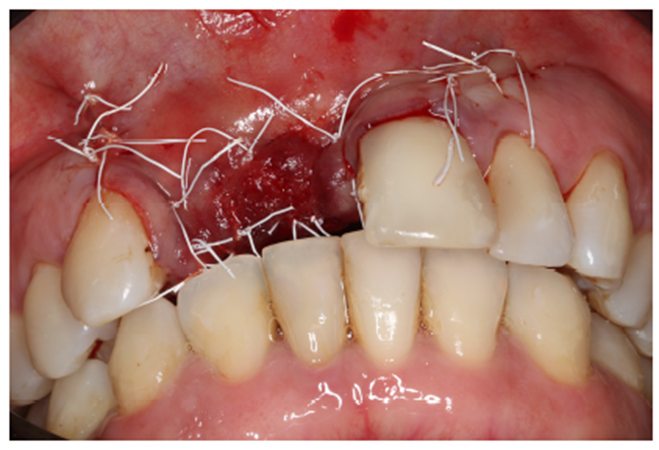

Ao exame clínico observou-se a ausência parcial dos dentes na maxilar e uma prótese parcial removível nos dentes 21 e 22, com extenso defeito em rebordo alveolar (Figura 1).

A escolha do fio é de extrema importância para o sucesso da cirurgia. Foi utilizado o fio de sutura de PTFE Cytoplast, cuja elasticidade acompanha o edema pós-operatório, diminuindo o risco de deiscência de sutura (Figuras 10 e 11).